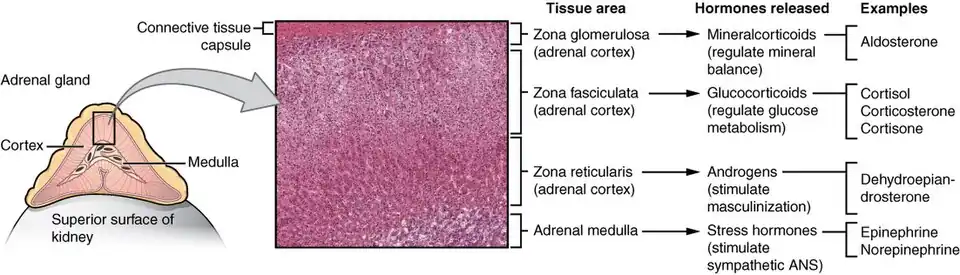

| Adrenal Glands Zonations | |

| Adrenal Glands Zonations | |

Study of the reported cases indicate that most adrenocortical adenomas occur due to neoplastic proliferation of adrenal cortical cells within the three distinct layers of adrenal cortex. In humans, the adrenal cortex comprises three concentric zones including the zona glomerulosa, zona fasciculata, and zona reticularis that under normal conditions respond to body's physiological demands for steroid hormones. The adrenal cortex is considered a dynamic organ in which senescent cells are replaced by newly differentiated cells. This constant renewal facilitates organ remodeling which contributes to dynamic characteristics of the adrenal cortex. [7] correspondingly, the developmental physiology of the adrenal cortex is believed to play a pivotal role in formation of the adrenocortical tumors. Hence, the molecular mechanisms involved in normal development of the adrenal glands are like double edged swords that can lead to the formation of tumors within the adrenal cortex. Moreover, recent studies suggest that mutations affecting the molecular pathways of the adrenocortical region can stimulate abnormal proliferation and tumor formation. Through these studies, the cyclic AMP-dependent protein kinase A signaling has been identified as a key mediator of cortisol secretion, and the mutations associated with the dysregulation of cyclic AMP - protein kinase A pathways have been implicated in the adrenocortical pathophysiology.[8]

If functional, adrenocortical adenomas can affect the normal activities of the adrenal cortex. Located within the adrenal glands are the three zones that are responsible for secretion of the three major classes of adrenal steroids. Hence, functional adrenocortical adenomas can induce over-secretion of adrenal steroids associated with pure or mixed endocrine syndromes, a condition commonly known as hyperadrenalism.